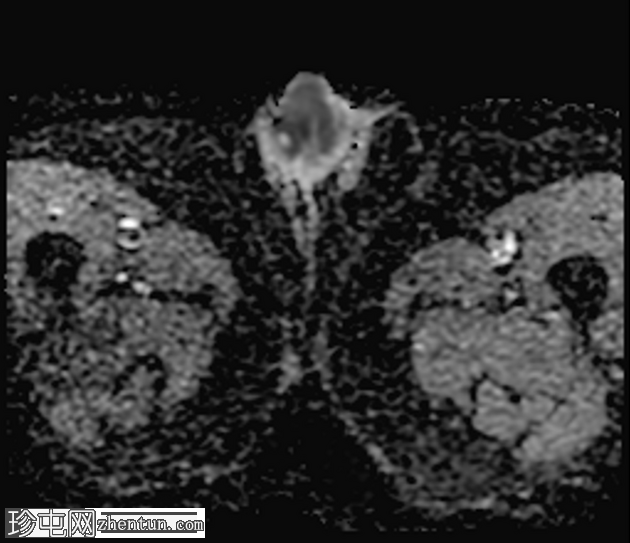

轴位

DWI

龟头可见不规则形状的软组织肿块,增强后明显强化,并伴有扩散受限。该肿块侵犯尿道海绵体,导致远端尿道狭窄和上游尿道扩张。

左侧腹股沟可见多个肿大的病理性淋巴结,右侧可见较小的非特异性淋巴结。